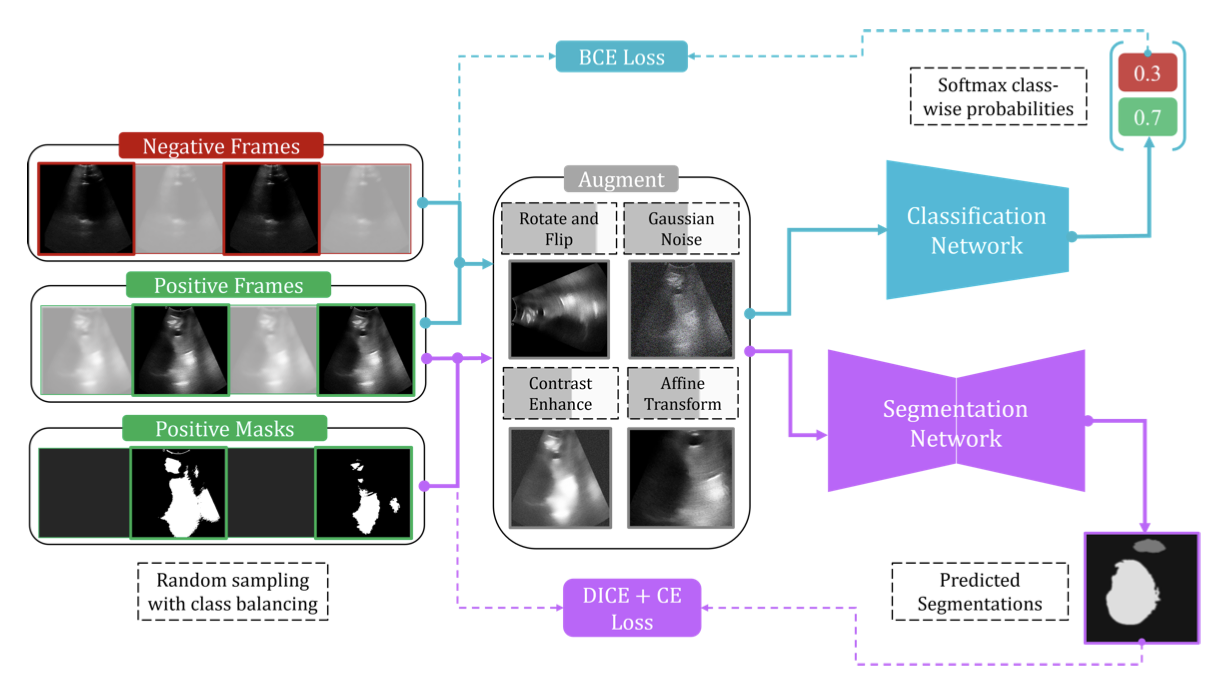

Beyond benchmarks of IUGC: Rethinking requirements of deep learning method for intrapartum ultrasound biometry from fetal ultrasound videos

Medical Image Analysis

·

01 Jun 2026

·

doi:10.1016/j.media.2026.104043